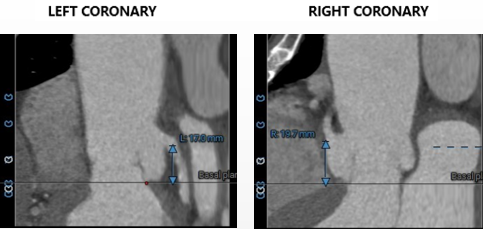

• 左右冠脉开口高度可,瓣叶长度均小于冠脉开口下缘到瓣叶附着缘位置,左冠脉可见少量散在钙化。

冠脉高度、瓣叶长度及左室内径:

冠脉高度可,未见冗长瓣叶,左室内偏径大,横位心(71°)